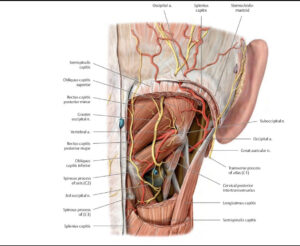

Nervo di Arnold e emicrania

Un’anomala retrazione di questi muscoli può comprimere il nervo grande occipitale (nervo di Arnold). Questo nervo esce dalla radice C2 e anastomizza con C1 e C3. Innerva alcuni muscoli di zona e la sua parte sensitiva si dirama verso l’occipite e verso l’apice della testa. In questa posizione presenta un’anastomosi con la branca oftalmica del trigemino. Una compressione di questo nervo quindi può recare sensazioni dolorose lungo il decorso della parte sensitiva, generando un’emicrania che può dirigersi fino all’occhio, causando anche emicrania con aurea.

Ganglio cervicale superiore

Anteriormente alle masse trasverse di C2 sono presenti i gangli cervicali superiori. Questi gangli fanno parte della catena del sistema ortosimpatico e presentano anastomosi con il nervo vago, il glossofaringeo e l’ipoglosso. Oltre a questi collegamenti, dal ganglio diparte il nervo carotico interno che segue la carotide interna (funzione vaso motrice) e forma il plesso carotideo. Da questo plesso origina una radice del ganglio ciliare che si dirige verso il bulbo oculare. Sempre da questo ganglio origina il nervo carotico esterno, i rami faringei per il plesso faringeo e il nervo cardiaco superiore che partecipa alla formazione del plesso cardiaco. Inoltre sono stati scoperti anche nervi che si dirigono alle strutture dell’encefalo, influenzando funzioni intellettive come l’apprendimento, le onde cerebrali e la secrezione di ormoni come la melatonina. Per tutti questi collegamenti, una disfunzione della seconda vertebra cervicale quindi può influenzare la funzionalità di questi gangli generando vari tipi di sintomi tra ipertensione arteriosa, dolore all’occhio, difficoltà ad addormentarsi, rallentamento dell’apprendimento.

Riflesso vestibolo-oculomotorio

I muscoli sub occipitali e i muscoli oculari sono interconnessi. Il posizionamento e il movimento della testa, governati in gran parte dai muscoli sotto occipitali situati alla base del cranio, sono essenziali per mantenere l’equilibrio o la visione chiara. Questi muscoli svolgono un ruolo cruciale nel regolare la posizione e l’orientamento della testa. Questo aggiustamento è fondamentale non solo per l’equilibrio, ma anche per garantire che i nostri occhi siano correttamente allineati all’orizzonte o a qualsiasi obiettivo specifico su cui ci stiamo concentrando. Quando i nostri occhi si muovono per guardare cose diverse, specialmente per molto tempo o quando ci sforziamo di vedere qualcosa, la nostra testa regola leggermente la sua posizione per aiutare gli occhi a concentrarsi meglio. Tutto questo processo si verifica perché quando i muscoli sotto occipitali regolano la posizione della testa, i vestiboli segnalano al nucleo vestibolare il cambiamento di posizione. Questa informazione giunge ai nuclei oculomotori, i quali mandano informazioni ai muscoli oculari tramite i nervi cranici deputati al movimento oculare (oculomotore III, trocleare IV, abducente VI) in modo da regolare la posizione della testa con la vista. In caso di squilibrio muscolare oculare, dove uno o più muscoli dell’occhio sono più deboli o più forti di altri, può esserci una risposta compensativa nei muscoli sotto occipitali. Questo può causare un aumento della tensione nei muscoli sotto occipitali, portando a dolori cervicali, mal di testa, cambiamenti posturali e problematiche legate alla vista. Al tempo stesso anche un eccessivo sovraccarico dei muscoli sotto occipitali, dovuto ad esempio a scompensi posturali, può causare un disequilibrio con i muscoli oculari e riportare i sintomi descritti in precedenza.